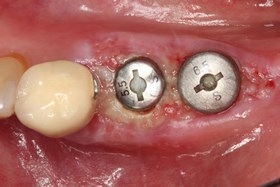

分別植牙後X光片

植牙後癒合狀況良好